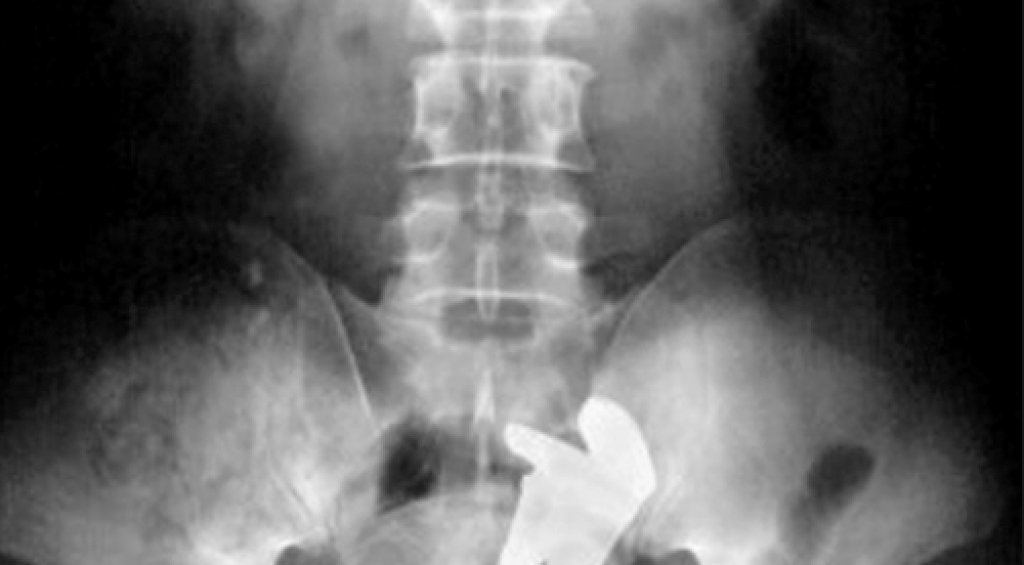

Е, той не може, но тези снимки говорят сами за себе си. И за хората, чиито са. Хора с (меко казано) доста извратени сексуални фантазии.

Тези осем примера показват това, което рентгенът не може да каже и затова докторите го правят вместо него. Вижте ги в галерията.